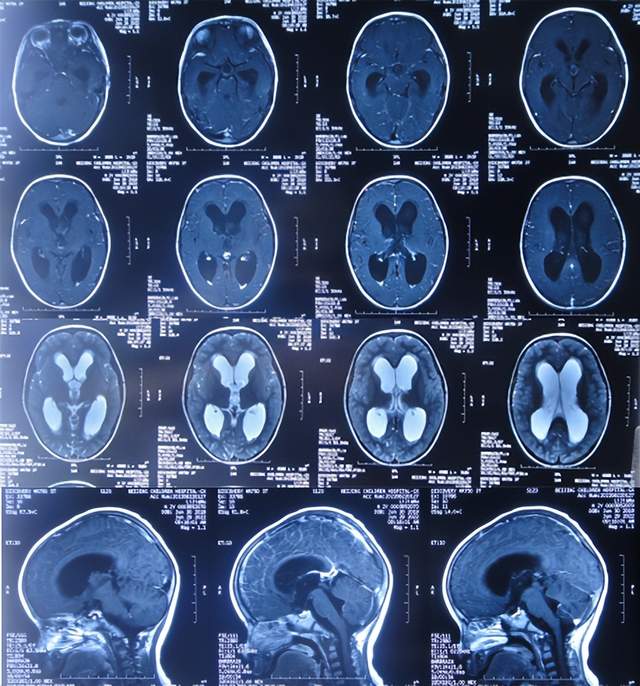

第3家医院治疗16天即2022年6月9日,不但依然发热,而且查头颅CT示脑室稍扩张(图-3)。

图-3:2022年6月9日头颅核磁

在第3家医院治疗24天即2022年6月17日,因病情仍无改善,在医生建议下转入了第4家医院北京更高级的三甲医院,给予消炎、脱水、改善心肌供血。

该院治疗11天期间,体温变正常,期间两次查脊髓核磁(图-4、图-5)示脊髓栓系松解术后。

图-4:2022年6月23日脊髓核磁

图-5:2022年6月28日脊髓核磁

但该院治疗12天即2022年6月29日,复查头颅核磁脑室扩张进一步加重(图-6)。

图-6:2022年6月29日头颅核磁